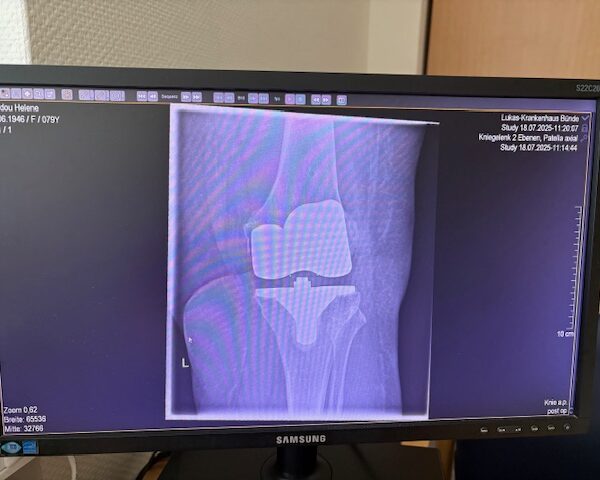

Η επέμβαση πραγματοποιήθηκε με ρομποτικά υποβοηθούμενη τεχνική, κατά την οποία το ρομποτικό σύστημα με καθοδήγησε με ακρίβεια χιλιοστού σε κάθε στάδιο.

Έτσι εξασφαλίστηκε η ιδανική τοποθέτηση των εμφυτευμάτων, η αποκατάσταση του μηχανικού άξονα και η διατήρηση των μαλακών ιστών.

Τα εμφυτεύματα που χρησιμοποιήθηκαν στο γόνατο της ασθενούς είναι της Aesculap: E-Motion Pro, μηριαίο μέγεθος 4, κνημιαίο μέγεθος 4, με ενθέμα (inlay) 10mm.